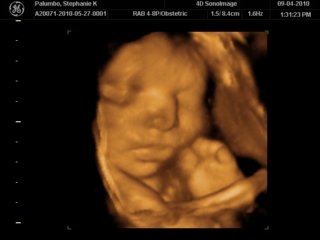

This was me back in early September